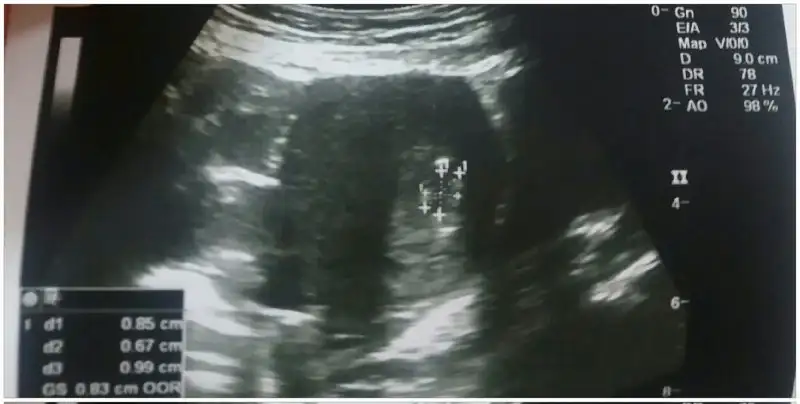

Hastaneden çıktım. Tsh için endokrinolojiye yönlendirdi doktorum. Bu da minik kesecik:nazar:

Bende minİk kesemi gördüm Allah’ıma bin şükür çok şükür